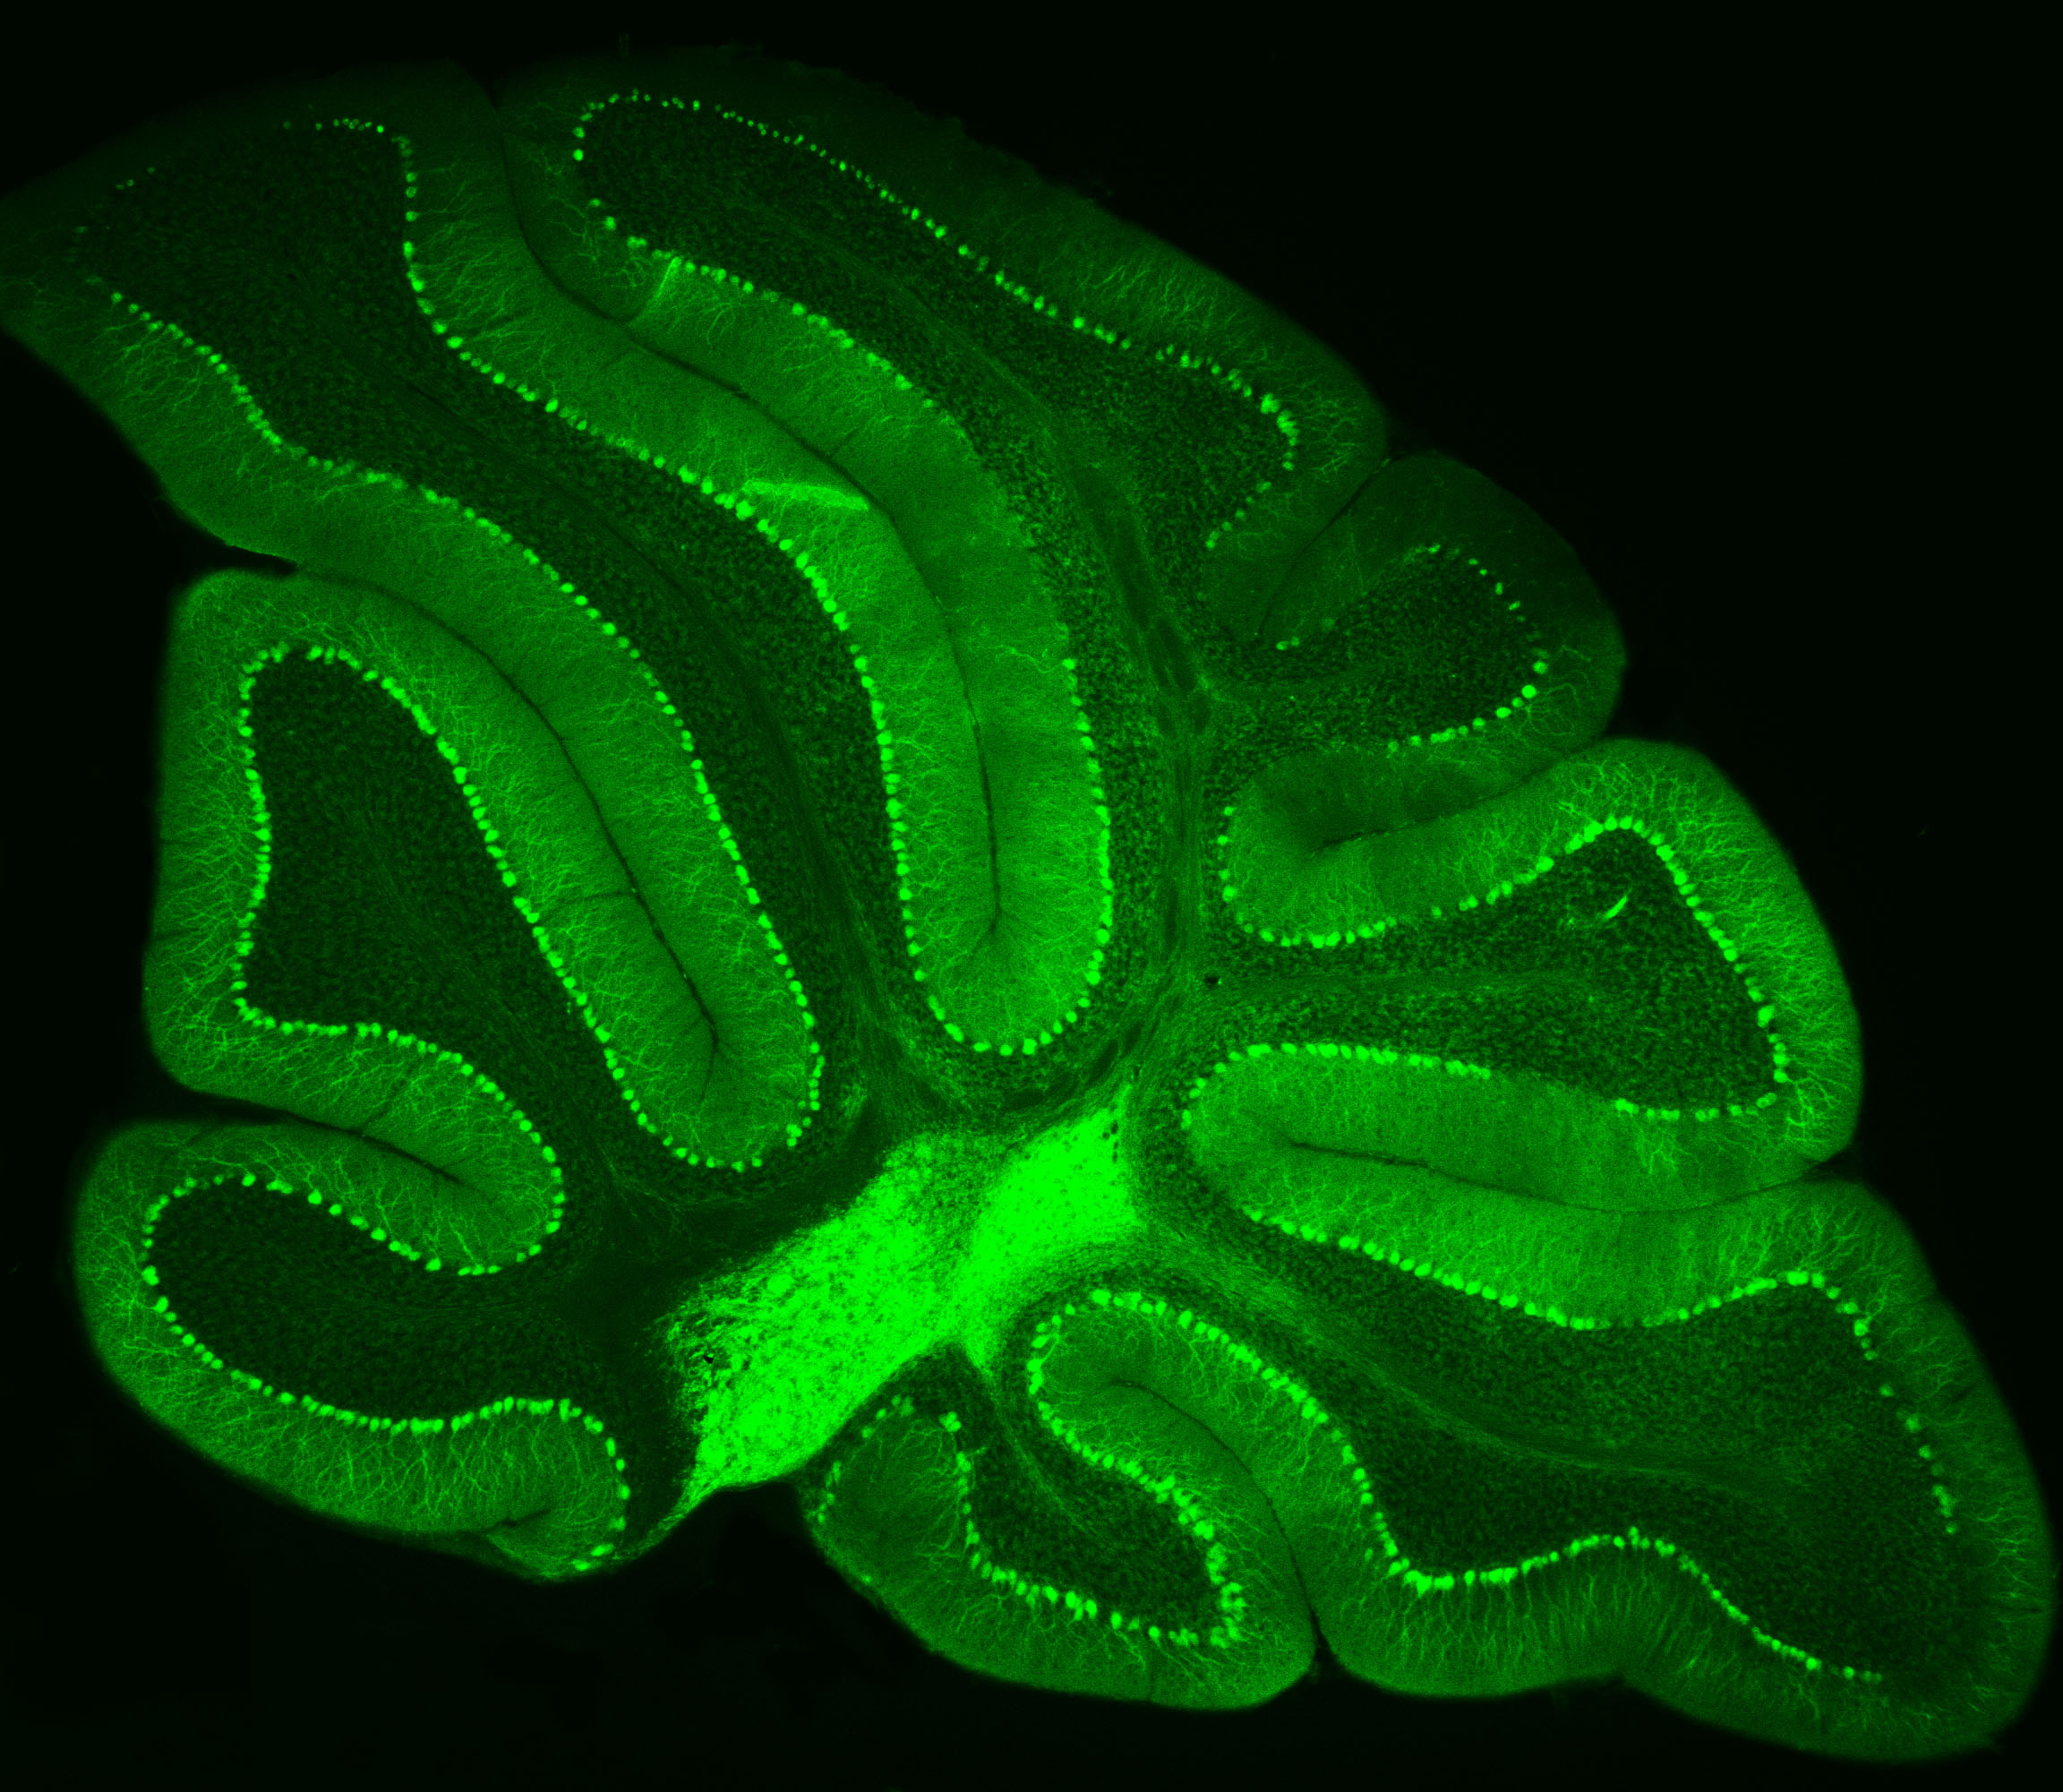

Purkinje neurons from an animal model are labeled with green fluorescent protein (GFP), which causes them to glow bright green.

– Credit: Pennington Biomedical

At Pennington Biomedical Research Center, scientists often study the brain by highlighting specific cells so they can be seen more clearly under a microscope. This technique was recently used by Dr. Yanlin He, associate professor and director of the Brain Glycemic and Metabolism Control Laboratory, who is examining Purkinje neurons in the cerebellum.

Purkinje neurons are best known for helping control movement and motor learning, but researchers are discovering they may have other important roles in the body as well, such as controlling energy balance and blood sugar.

By making these neurons glow green, Dr. He and his team can see their complex branching shapes and how they connect within the cerebellum’s neural network.

This technique also allows researchers to perform electrophysiology recordings, which measure the electrical activity of the cells in a laboratory setting. Their work could help scientists better understand how the brain helps regulate metabolism and overall health.